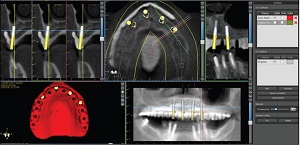

Implant planning begins with a jaw scan, cone beam computed tomography (CBCT) and a blood test. The dentist compares the results and determines the optimal position of the implants, the type of bone, the position of the dental system, the need for augmentation (bone buildup) or sinus lifting.